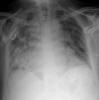

Fibrosis pulmonar. ICC.

Neumonia basal derecha.

Neumonía basal derecha.